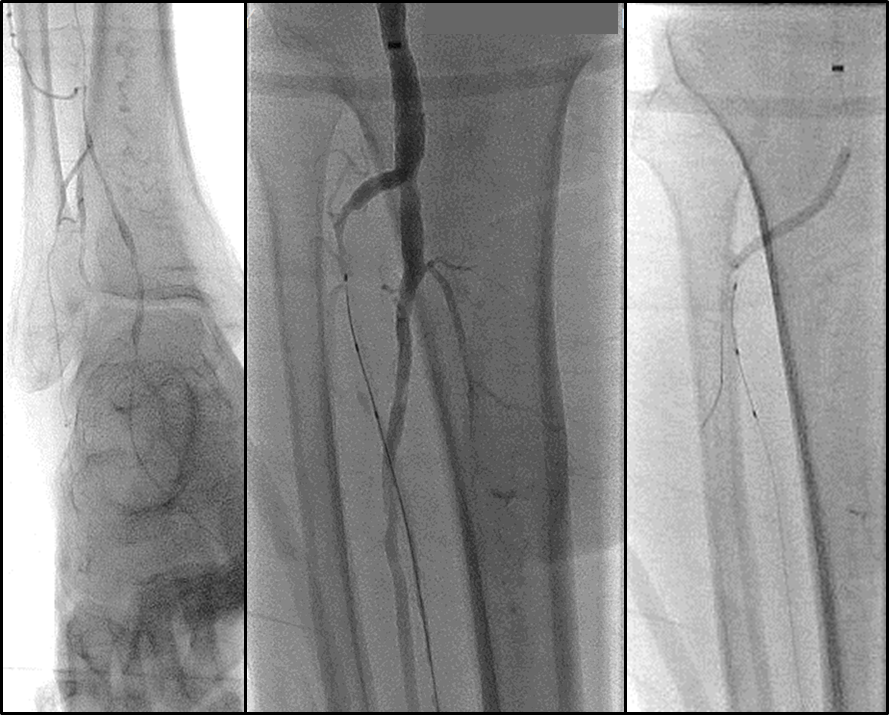

BTK病变多为长段、弥漫、钙化、CTO,多累及踝下(BTA)

各分支 CTO 解剖特点

三大主要分支的CTO近端与远端常见位置:

总体特点:

膝下通常有单个或数个可见的流入道;

病变常为单个或多个CTO组合,总长度可达20cm;

部分患者存在踝上交通动脉或完整的踝下足底弓,为逆向开通提供可能。